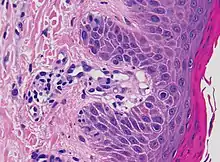

| Kaposi’s sarcoma in patch stage | The patch stage typically shows irregular proliferation of jagged vascular channels in the dermis below an integral epidermis. The so-called promontory sign is sometimes found in patch stage lesions and denotes vascular spaces surrounding pre-existing blood (see image).[23]

vessels |

|

|

| Not otherwise specified[notes 2] | A lesion with superficial lymphoplasmacytic infiltrate without additional histopathologic characteristics can be due to for example trauma, ulceration, scar and early cutaneous connective tissue diseases.[2][notes 2] |